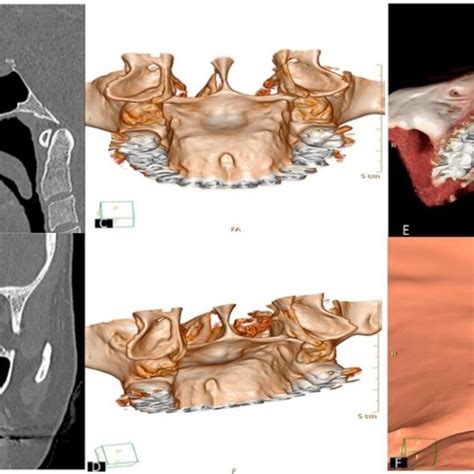

- Torus palatino: es una anomalía genética que cursa de forma asintomática y que no siempre requiere de una intervención. No en vano, muchos pacientes ignoran que padecen esta condición ya que no suele resultar molesta y no afecta a la estética de la boca.

- Torus palatino: es una protuberancia dura. Suele tener una causa genética, es asintomático y no duele. Por ello, muchos pacientes ni siquiera se dan cuenta de que lo tienen. Si es asintomático no se suele extirpar.